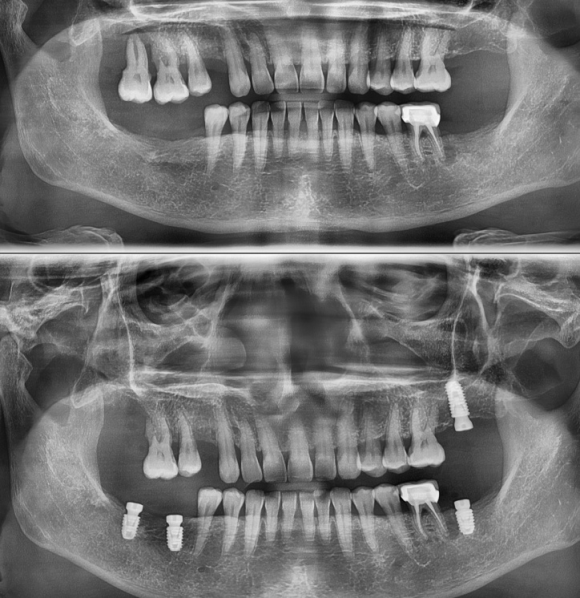

인천에서 오신 분 내과 당일 협진으로 전신 질환 (당요 등등) 확인 후 임플란트 식립. 뼈가 좋지 않아서 충분하게 분석 후 신경 손상을 피하기 위해 전략적이로 보수적으로 접근. 수술 후 3D 사진을 이용한 확인 완료. #상도동에서임플란트가장많이하는치과, #숭실대치과, #상도동치과, #동작구치과, #임플란트,...

인천에서 오신 분 내과 당일 협진으로 전신 질환 (당요 등등) 확인 후 임플란트 식립.

뼈가 좋지 않아서 충분하게 분석 후 신경 손상을 피하기 위해 전략적이로 보수적으로 접근.

수술 후 3D 사진을 이용한 확인 완료.